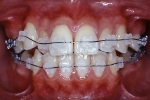

| 治療後3年経過時